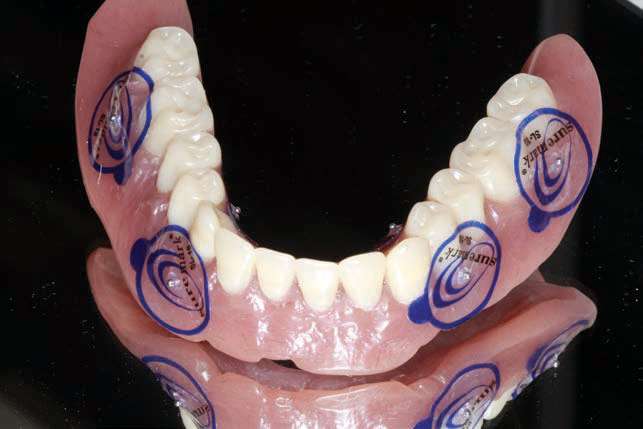

After the patient had the upper partial denture and lower denture fabricated and the vertical dimension of occlusion, aesthetics, and phonetics were verified, the approved lower denture was used as a vehicle for fiduciary markers so that a CBCT scan could be done. If needed, a surgical guide could be fabricated from a dual-scan protocol (Suremark) (Figure 4).

A wax-rim was sent for recording a maxilla-mandibular jaw registration (Figure 15), and then teeth were set, and a wax set-up (Glidewell Laboratories) was returned to evaluate phonetics, aesthetics, and verti-centric (Figure 16). A PMMA provisional implant prosthesis was fabricated and delivered, giving the patient an opportunity to verify the prosthetic design, aesthetics, and phonetics during function (Figure 17).